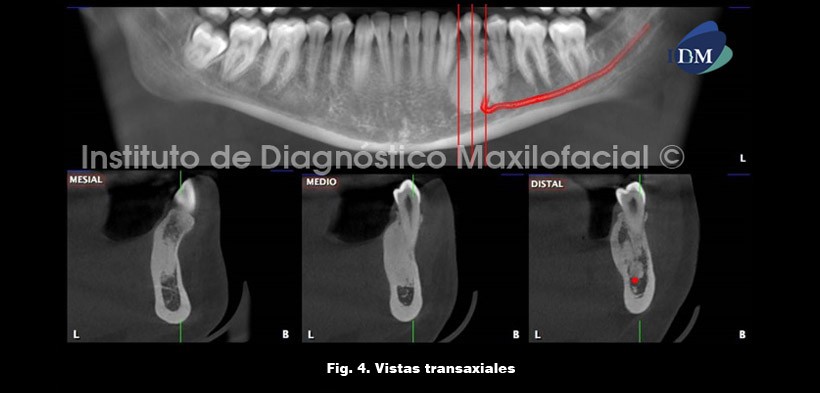

Las vistas transaxiales son ideales para evaluar la relación de la extensión de la entidad con las piezas dentarias. Por consiguiente, se aprecia una estrecha relación del segmento radicular de la pieza 34 con la zona osteoesclerótica (Fig. 4).